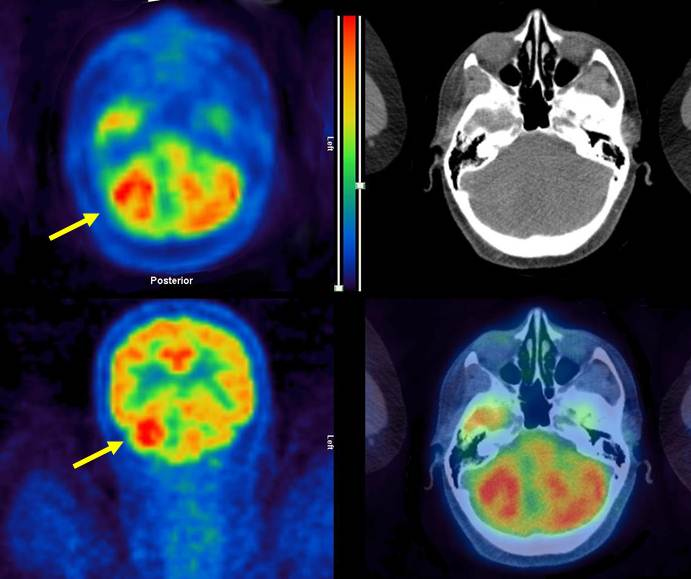

Además, se observó un área con incremento en la captación del radiotrazador en el hemisferio derecho del cerebelo. La masa mostraba un halo hipermetabólico acompañado de una zona central de posible necrosis, con un tamaño de 2,4x3,5x3 cm y SUVmax de 8,9 (SUV cerebelo: 6,6) siendo por tanto sugestiva de malignidad (fig. 2). Se evidenció también, un aumento patológico de captación en la glándula adrenal izquierda, con un tamaño de 1,5x2,5x3 cm y SUVmax de 7 (SUV del parénquima hepático: 3,4), por lo que se consideró también como sugestivo de malignidad (fig. 3).

Entre el 2-12% de pacientes con CRC desarrollan metástasis encefálicas durante el curso de la enfermedad(18). En nuestro caso, un examen neurológico posterior a los hallazgos en la PET/CT demostró expresión clínica cerebelosa (inestabilidad de la marcha). El deterioro neurológico y la accesibilidad de la lesión llevaron a la práctica de una metastasectomía, recibiendo posteriormente radioterapia holocraneal. La supervivencia media en estos casos oscila entre los 2,8 y 6 meses, independientemente de la terapia empleada para el tratamiento de las metástasis encefálicas(19).